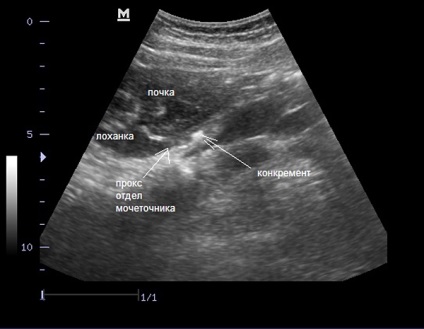

- jelenlétében vesekő;

- A kövek jelenlétét.

A fogkő a vesében